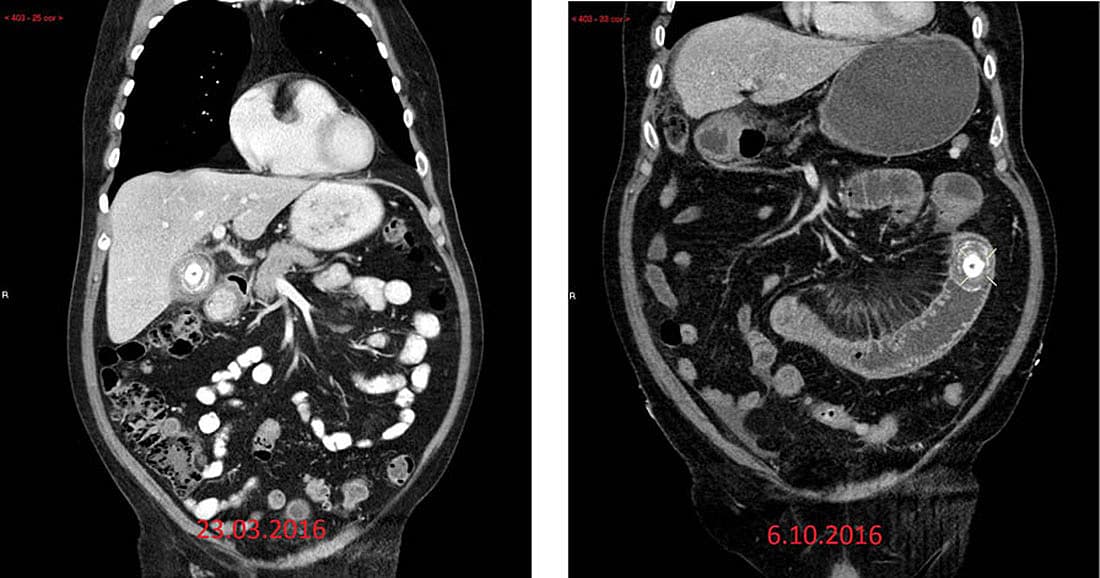

En 80-årig mand, som tidligere havde haft galdesten og leverabsces, blev indlagt pga. mavesmerter, opkastninger og manglende afføring gennem otte dage. Pga. forhøjede infektionstal og mistanke om absces blev der foretaget en CT af abdomen med i.v. kontrast, hvorved der sås tyndtarmileus pga. et stort konkrement. Derudover fandt man kolecystitis med perforation af galdeblæren samt luft i galdeblæren. En sammenligning med en tidligere CT af abdomen viste, at galdestenen havde flyttet sig til tyndtarmen gennem en fistel fra galdeblæren til duodenum. Efterfølgende havde konkrementet sat sig fast i tyndtarmen og resulteret i ileus. Patienten fik fjernet galdestenen, som målte 6 × 4 cm, og foretaget tyndtarmresektion med anastamose. Han blev udskrevet efter fire dage.

Galdestensileus blev første gang beskrevet i 1654 af Bartholini [1]. Det er en sjælden tilstand, som tegner sig for 1-4% af alle tilfælde af tyndtarmsobstruktion, men ses i op til 25% af alle tilfældene hos patienter over 65 år [2]. Tarmobstruktion kan være betinget af ektramurale, intramurale eller intraluminale årsager. Galdestensileus er en intraluminal obstruktion, som er forårsaget af galdesten, der passerer gennem en fistel mellem galdeblæren og duodenum. Klinisk havde patienten Mordors triade: en sygehistorie med galdesten, kliniske tegn på kolecystitis og pludselig opstået tarmobstruktion. CT har sensitivitet, specificitet og diagnostisk præcision på hhv. 93%, 100% og 99% [3, 4]. Riglers t riade, dvs. pneumobilia, tyndtarmileus og galdesten, er et typisk radiologisk fund ved galdestensileus [3].